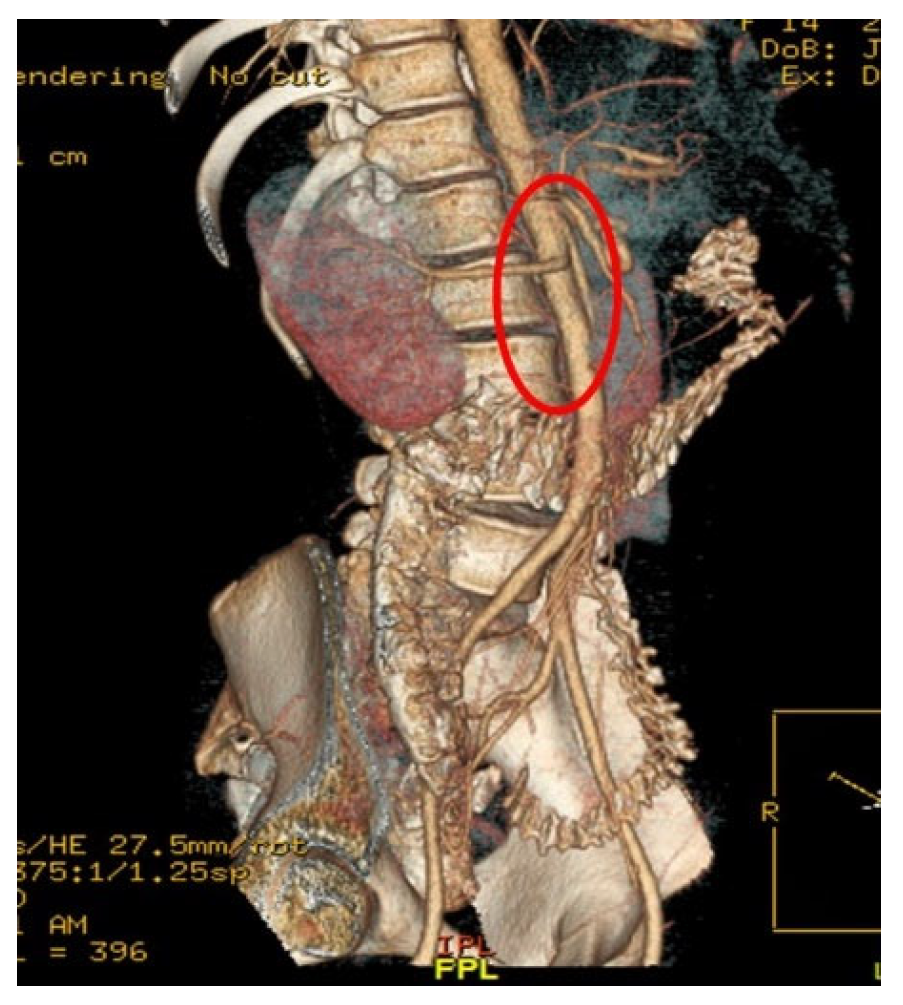

Computed Tomography Angiography (CTA) Figure 2, provided definitive anatomical correlation. At the level where the third portion of the duodenum crosses between the abdominal aorta and the SMA, the aortomesenteric angle was significantly reduced to 6° (normal: 38–56°), Figure 3 and the aortomesenteric distance measured 4 mm (normal: >10 mm, with <8 mm considered pathological). Figure 4 These findings were consistent with SMAS, a rare condition caused by vascular compression of the third portion of the duodenum between the SMA and the aorta.

Figure 4. CTA: Findings consistent with superior mesenteric artery SMAS.